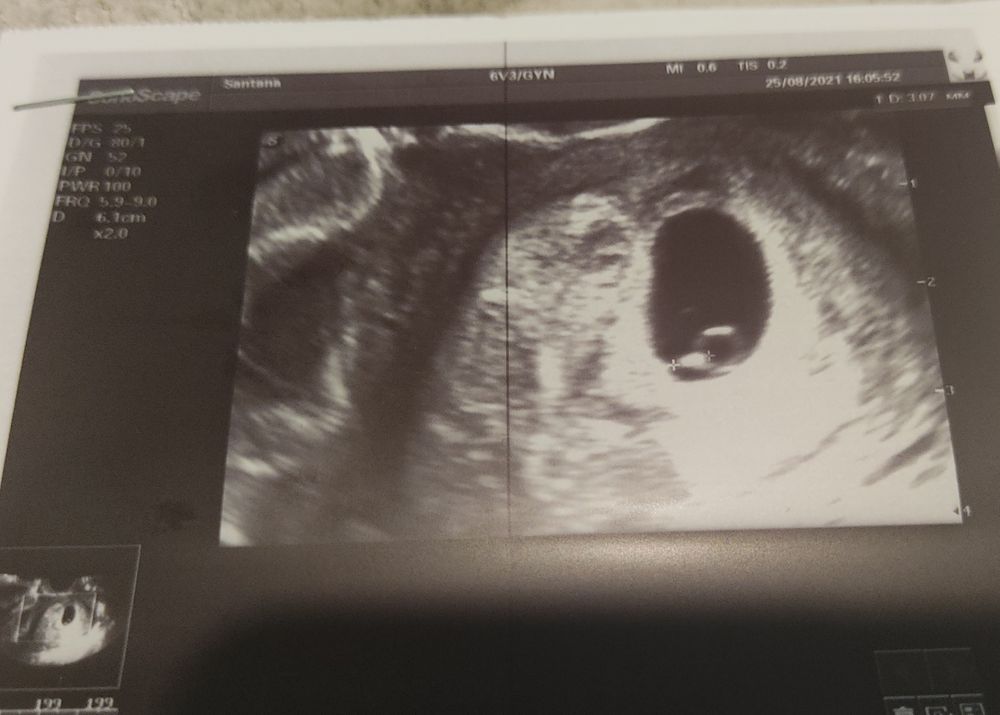

Первое УЗИ (мое колечко)))

Сегодня по календарю ровно 6 ак.нед.) сходила на первое УЗИ, чтобы сердце свое успокоить)) малыш там, где ему нужно быть!)ура😍 увидела пульсацию сердечка❤️ и свое драгоценное"колечко с бриллиантом")

Срок эмбр. - 3 нед. 3 дня. Через недели две можно будет сердечко послушать.